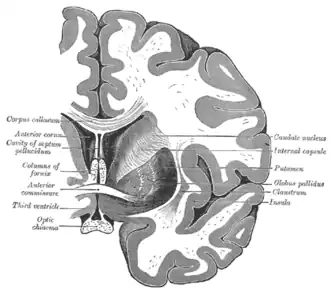

Coronal section through anterior cornua of lateral ventricles. -

Coronal section of brain through anterior commissure. -

Structure

Along with the putamen, the caudate forms the dorsal striatum, which is considered a single functional structure; anatomically, it is separated by a large white-matter tract, the internal capsule, so it is sometimes also described as two structures—the medial dorsal striatum (the caudate) and the lateral dorsal striatum (the putamen). In this vein, the two are functionally distinct not because of structural differences, but merely because of the topographical distribution of function.

The caudate nuclei are near the center of the brain, sitting astride the thalamus. There is a caudate nucleus in each hemisphere of the brain. Each nucleus is C-shaped, with a wider "head" (caput in Latin) at the front, tapering to a "body" (corpus) and a "tail" (cauda). Sometimes a part of the caudate nucleus is called the "knee" (genu).[6] The caudate head receives its blood supply from the lenticulostriate artery; the tail of the caudate receives its blood supply from the anterior choroidal artery.[7]

The head and body of the caudate nucleus form part of the floor of the anterior horn of the lateral ventricle. The body travels briefly towards the back of the head; the tail then curves back toward the anterior, forming the roof of the inferior horn of the lateral ventricle. This means that a coronal section (on a plane parallel to the face) that cuts through the tail will also cross the body and head of the caudate nucleus.